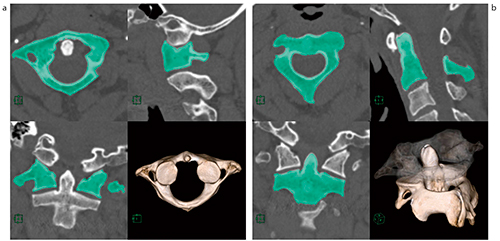

セグメンテーションツールは従来,「造影血管と骨を分離するもの」と認識されることが多いが,当社のリージョングローイングは,あらゆるものの分離・分割が可能である。頭頸部領域では,脊柱管や椎体に対する画像診断も非常に多く,頸椎のすべりや,椎間板のヘルニアなどではさまざまな症状が生じる。診断の際には,骨の形状や上下との連結関係など,さまざまな部分が注目されるが,断層画像のみでは治療する外科医にとって構造をイメージすることが難しかった。以前からも,椎体を分離してわかりやすく表示するという取り組みがあったが,当社のリージョングローイング機能では,ワンクリックで指定した椎体を抽出することが可能である(図3)。当技術は,物体,骨の種類などを限定しておらず,再現性高くあらゆる物体を分離することが可能である。

図3 リージョングローイング機能による椎体の抽出

a:環椎 b:軸椎

閾値によらない抽出は再現性を高める。